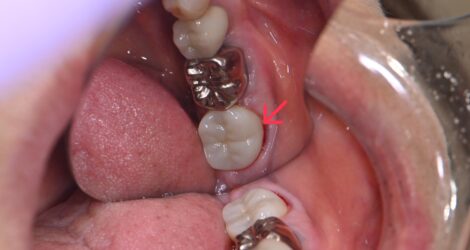

銀歯が外れたら中が虫歯に…

みなさんこんにちは!歯科衛生士の高橋です🦄 今回はクリーニング中にフロスを通したら銀歯がポロッと取れてしまった患者様の症例です。 外れた箇所を見ると、中に汚れが詰まっていて虫歯になっていました💦 神経が無い歯なのでしみるといった症状はありませんでしたが、残っている歯が薄くなっていたため、土台を立てて歯全体を覆うクラウンタイプで処置をすることにな …

みなさんこんにちは!歯科衛生士の高橋です🦄 「フロスを通すと引っかかってボソボソする」そんな経験ありませんか? もしかしたらそれは虫歯になってるからかもしれません😱 古い詰め物が歯と歯の間にあり、フロスを通すと引っかかって気になるとのことで、詰め物を削ったら中が虫歯になっていました💦(ピンク色に染まっている所が虫歯です😈) 虫歯を取っていくと …